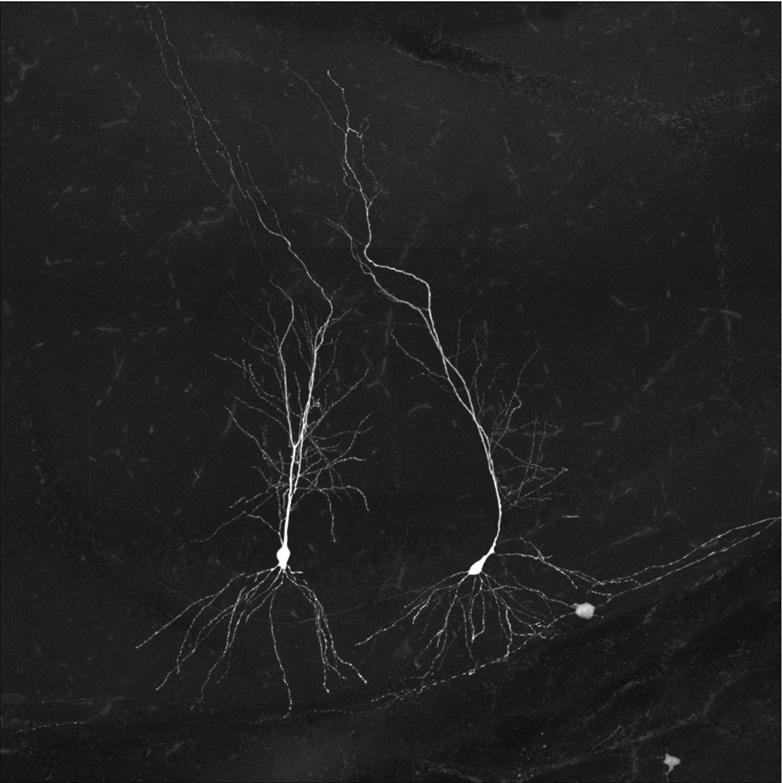

We have a shared objective to discover why neurons are lost in dementia-associated conditions. Credit: Gan Lab